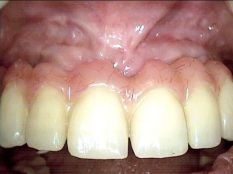

Patiente ayant fracturé sa dent suite à un choc. L’implant est mis en place après

une courte période de cicatrisation de la zone traumatisée. Une couronne provisoire en résine

est placée le jour de l’intervention (vue clinique après 6 semaines).